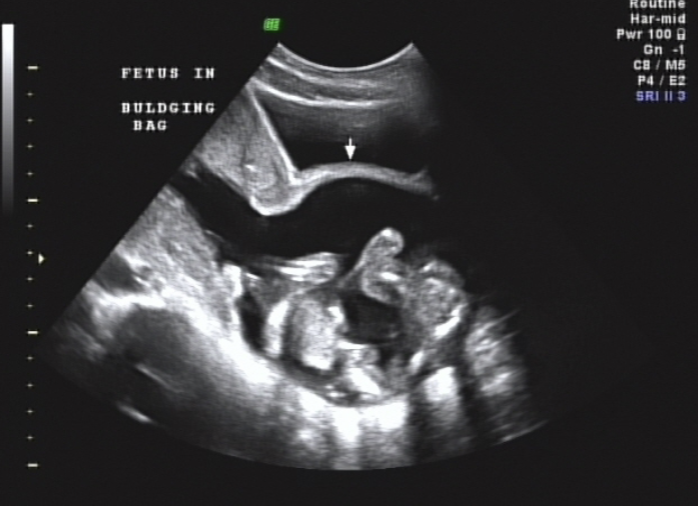

Incompetent Cervix

cervix may open and allow fetus to pass into vaginal canal → Bulging Bag (BBM)

Hour-glassing

If enough cervix remains, a cerclage may be put in place to “stitch” the cervix closed in effort to prevent Preterm delivery (PTD)

would not place cerclage in the presence of major fetal anomaly, PROM, infection or placental abruption